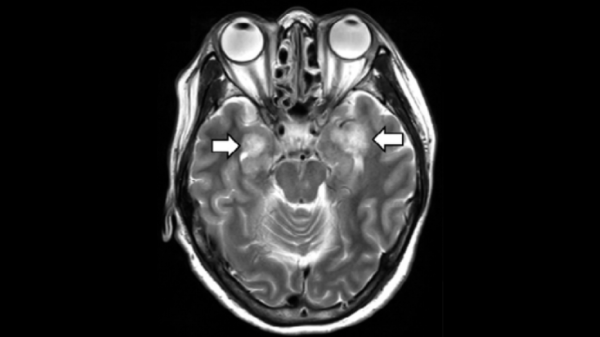

Дослідження, опубліковане у квітні 2025 року у відомому журналі Nature, виявило переконливі докази того, що вакцина проти оперізувального лишаю може знизити ризик деменції у населення загалом на цілих 20%.

Дослідники використали зміну політики як своєрідну природну лабораторію для вивчення впливу вакцинації проти оперізувального лишаю на довгострокові показники здоров’я. У статистично складному аналізі медичних записів команда виявила, що вакцина знизила ймовірність розвитку деменції на одну п’яту протягом семи років. Це означає, що люди, які отримали вакцину проти оперізувального лишаю, мали меншу ймовірність розвитку клінічної деменції протягом семирічного періоду спостереження, і жінки отримали більше користі, ніж чоловіки.

Одним з наукових пояснень зниження ризику деменції завдяки вакцині проти оперізувального лишаю може бути прямий захист від вірусу оперізувального лишаю, який може відігравати певну роль у загостренні деменції.

Однак, існує також ймовірність того, що вакцина могла забезпечити захист, активуючи імунну систему та забезпечуючи «тренований імунітет», коли імунна система зміцнюється внаслідок багаторазового впливу вакцин або вірусів.

У дослідженні не розрізняли різні типи деменції, такі як деменція, спричинена хворобою Альцгеймера, або деменція, спричинена інсультом. Крім того, дослідники не можуть зробити жодних остаточних висновків щодо можливих механізмів захисту вакцин лише на основі аналізу медичних записів.

На жаль, протягом останніх двох-трьох десятиліть амілоїдна гіпотеза хвороби Альцгеймера, яка стверджує, що накопичення білка під назвою амілоїд у мозку сприяє цьому розладу, домінувала в наукових дискусіях. Як наслідок, більшість зусиль в експериментальній терапії хвороби Альцгеймера були зосереджені на препаратах, що знижують рівень амілоїду в мозку.

Однак, результати на сьогоднішній день є скромними та невтішними. Дві нещодавно схвалені терапії для зниження рівня амілоїду мають лише мінімальний вплив на уповільнення спаду, є дорогими та мають потенційно серйозні побічні ефекти. І жоден препарат, наразі схвалений Управлінням з контролю за продуктами харчування та лікарськими засобами для клінічного використання, не повертає когнітивний спад.